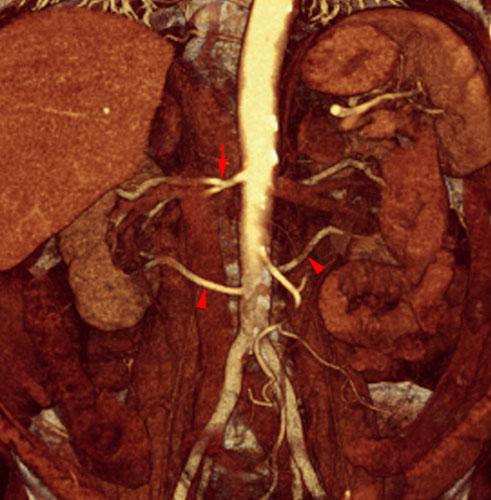

Arterias renales múltiples

Arterias renales accesorias

Arterias renales polares